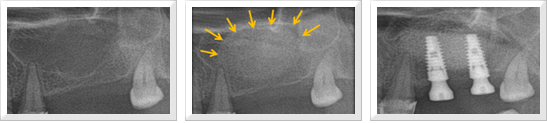

위턱에 잇몸뼈가 많이 흡수되어 상악동 (코 양쪽에 있는 공기가 차 있는 공간)과의 거리가 가까워 임플란트 식립이 어려운 경우 상악동 내에 골 이식술을 시행하여 임플란트 식립을 위한 충분한 뼈를 확보하기도 합니다.

이 경우 상악동에 있는 점막을 들어 올리고 점막과 상악동 바닥 사이에 골 이식을 하고 임플란트를 식립할 수 있습니다. 상악동 측벽에 조그마한 창문을 만들고 상악동 바닥을 덮고 있는 점막을 상방으로 거상하여 그 사이에 뼈를 이식하는 방법이 있습니다. 6-9개월 후 뼈가 아문 뒤 임플란트를 식립하게 됩니다.

잔존하고 있는 잇몸뼈의 양에 따라 뼈 이식과 동시에 임플란트를 시하기도 합니다.

상악동 골 거상술을 이용한 골 이식술과 임플란트 시술 도해

상악동 골 거상술을 이용한 이식술과 임플란트 시술 과정

위턱과 상악동과의 거리가 충분하지는 않으나 어느정도 뼈가 보존된 경우 상악동에 측벽에 창문을 만들 필요 없이 임플란트 식립 부위를 형성한 뒤 이를 통해 골 이식재를 상악동내에 넣어서 뼈이식술을 시행하고 곧바로 임플란트를 식립할 수도 있습니다.